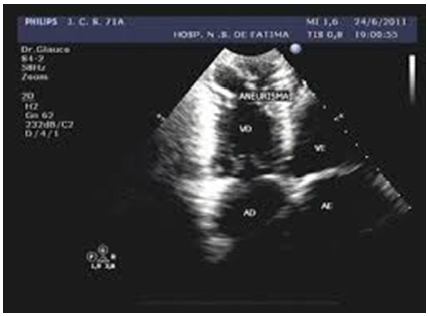

Paciente, 33 anos, com quadro de intolerância

aos esforços e palpitações por episódios de

taquicardia supraventricular, apresentou um

episódio de acidente vascular cerebral há

duas semanas. Em relação à imagem a seguir

e ao caso clínico apresentado, assinale a

alternativa INCORRETA.